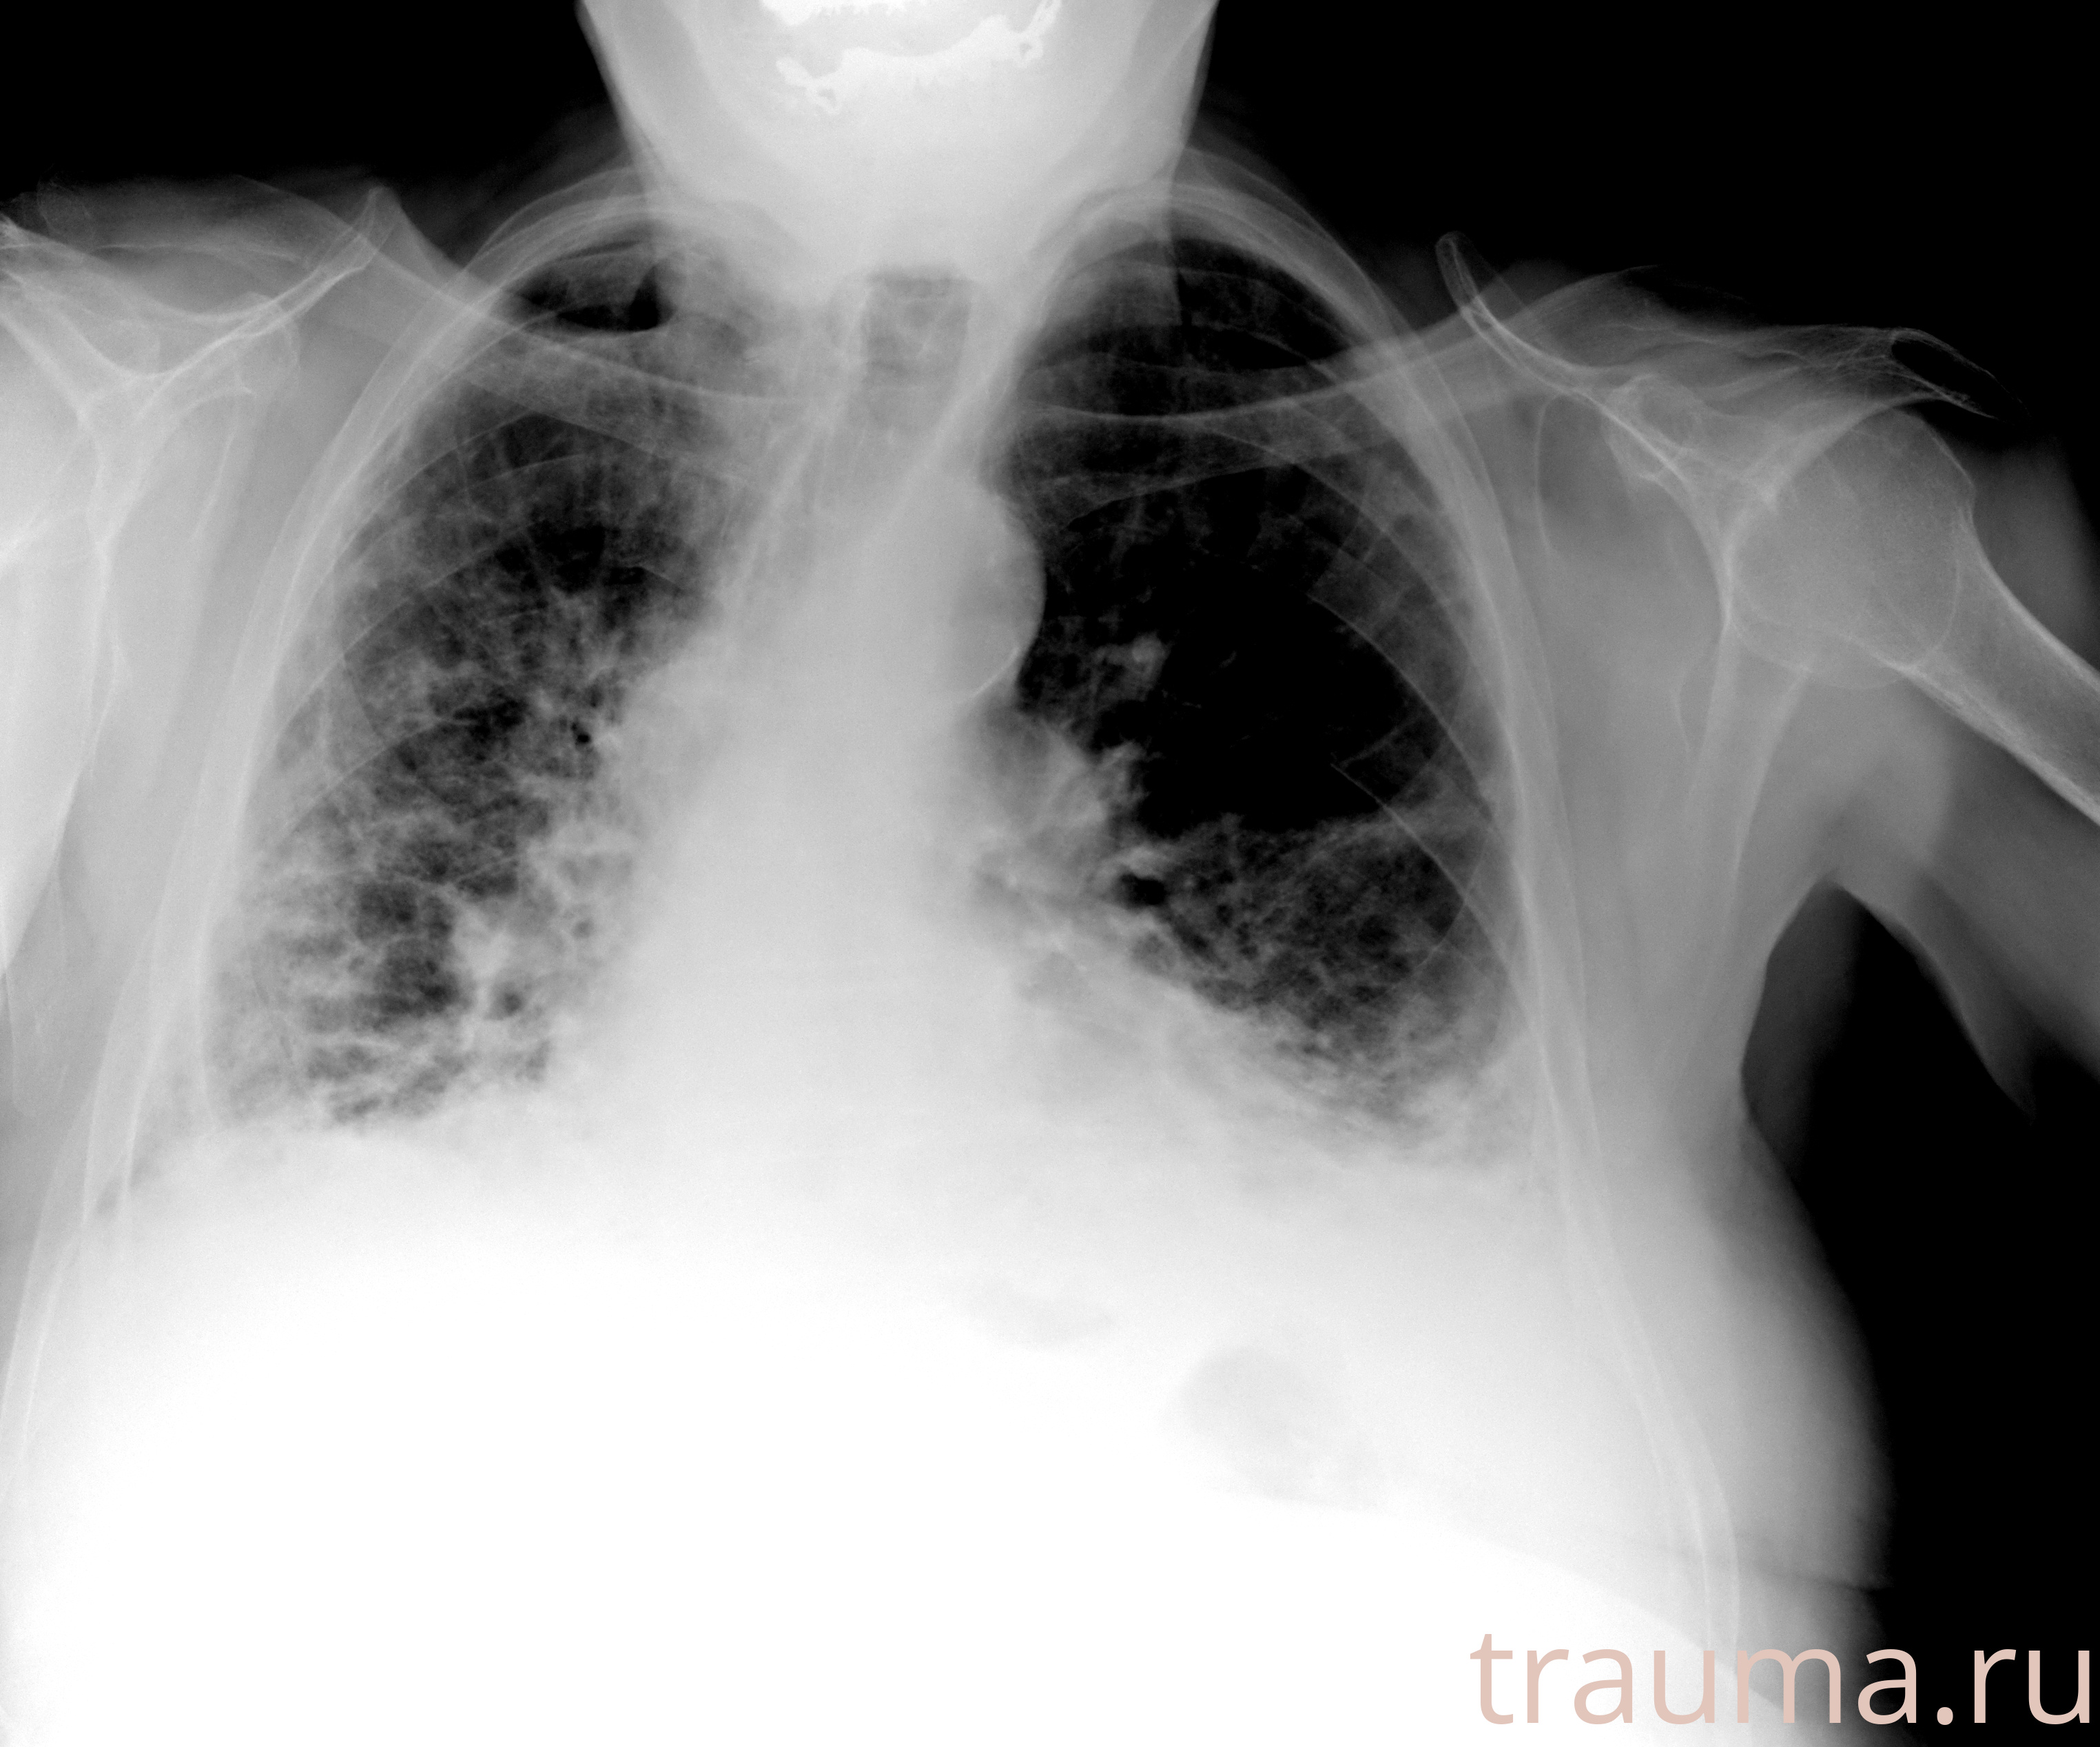

Рентген на дому: по вашему адресу приезжает врач-рентгенолог, травматолог-ортопед с мобильным рентгеновским аппаратом, проводит диагностику травмы или заболевания, делает необходимые рентгенограммы, дает рекомендации по дальнейшему лечению. Получить качественные снимки в домашних условиях возможно благодаря уникальной методике, разработанной МосРентген Центром для института  Склифосовского

при переломе шейки бедра и пневмонии от компании МосРентген Центр - партнера Института имени Склифосовского